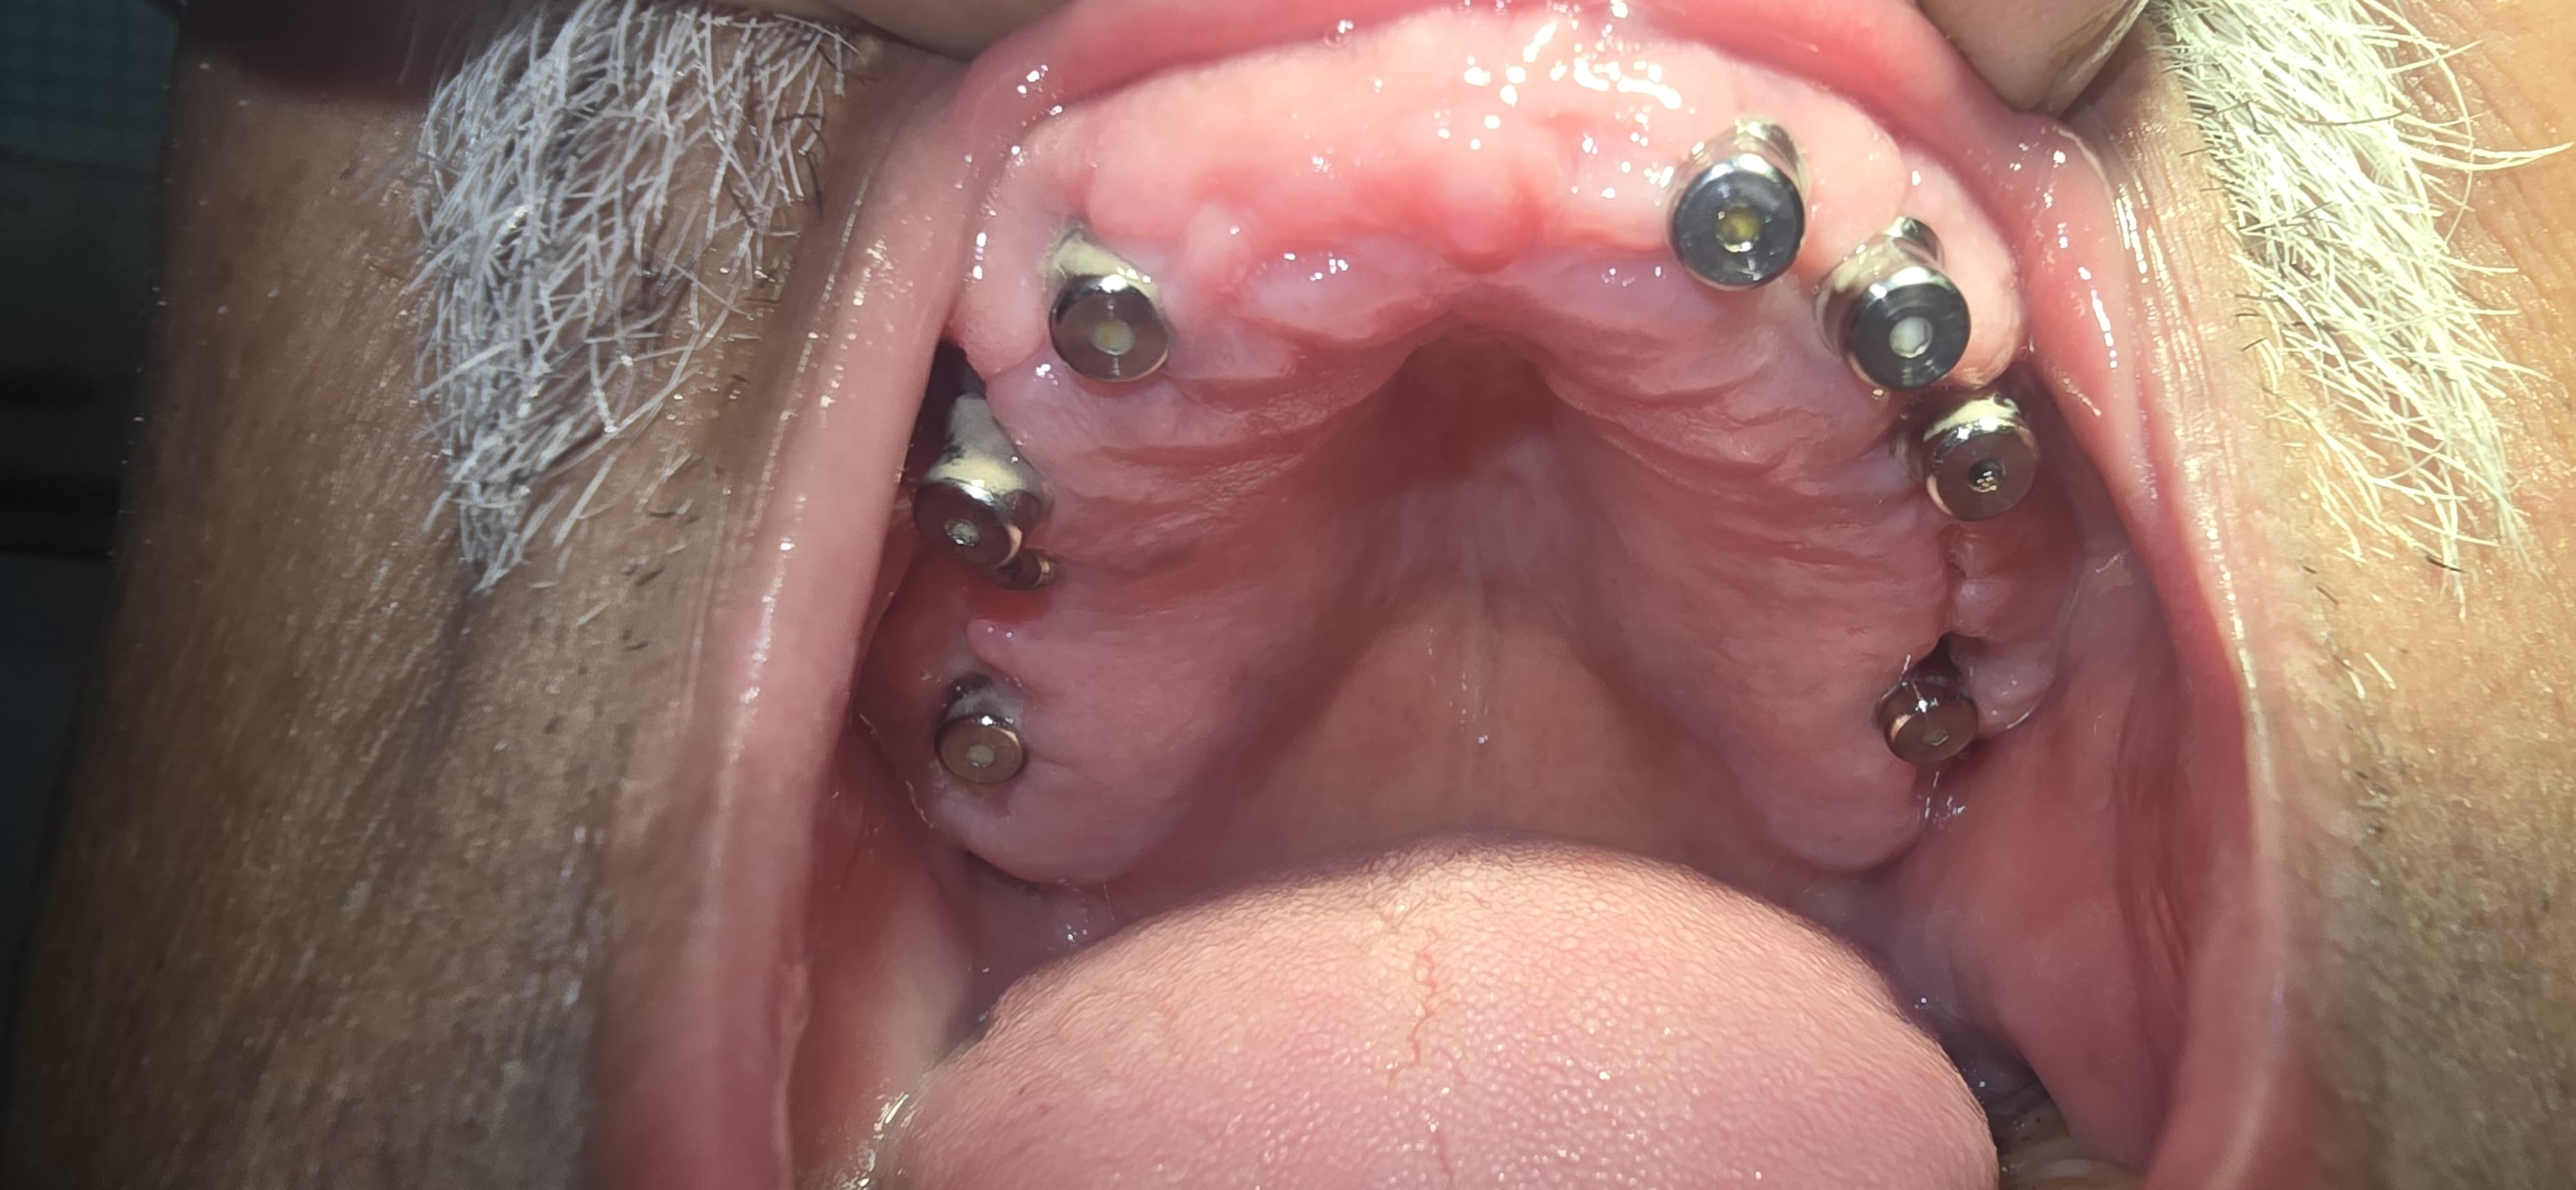

Full Mouth Implant Case

Full Mouth Implants with all Ceramic Crowns